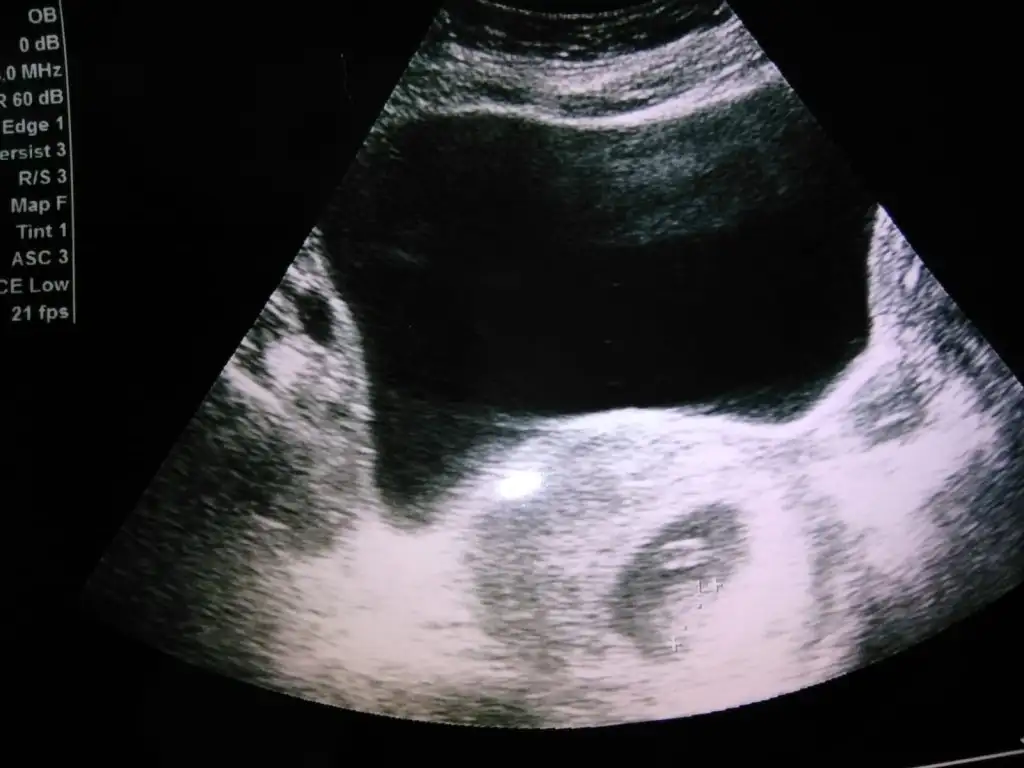

6-9 Haftalardaki ultrason görüntüsü varsa gönder beni etiketle yorumlıyım canım burda büyük ben bu şekilde anlamıyorumBanada 12 de erkek 16 da kız dedi anlayan varmı ultrasondan

Karındansa kız vajinelse erkek

6-8 haftalık ultrason fotosu varsa atın yorumlayayım burda bebek büyük, plesanta anlaşılmıyor10 haftalık bizede bakabilirmisinizEki Görüntüle 3210511

Ay inşlh Dr 11. Hafta kız gibi dedi 12. Haftada erkek gibi dedi çok kafam karıştı. Doğana kadar hep bi şüphe yaşayacağım herhaldeKarındansa kız vajinelse erkek